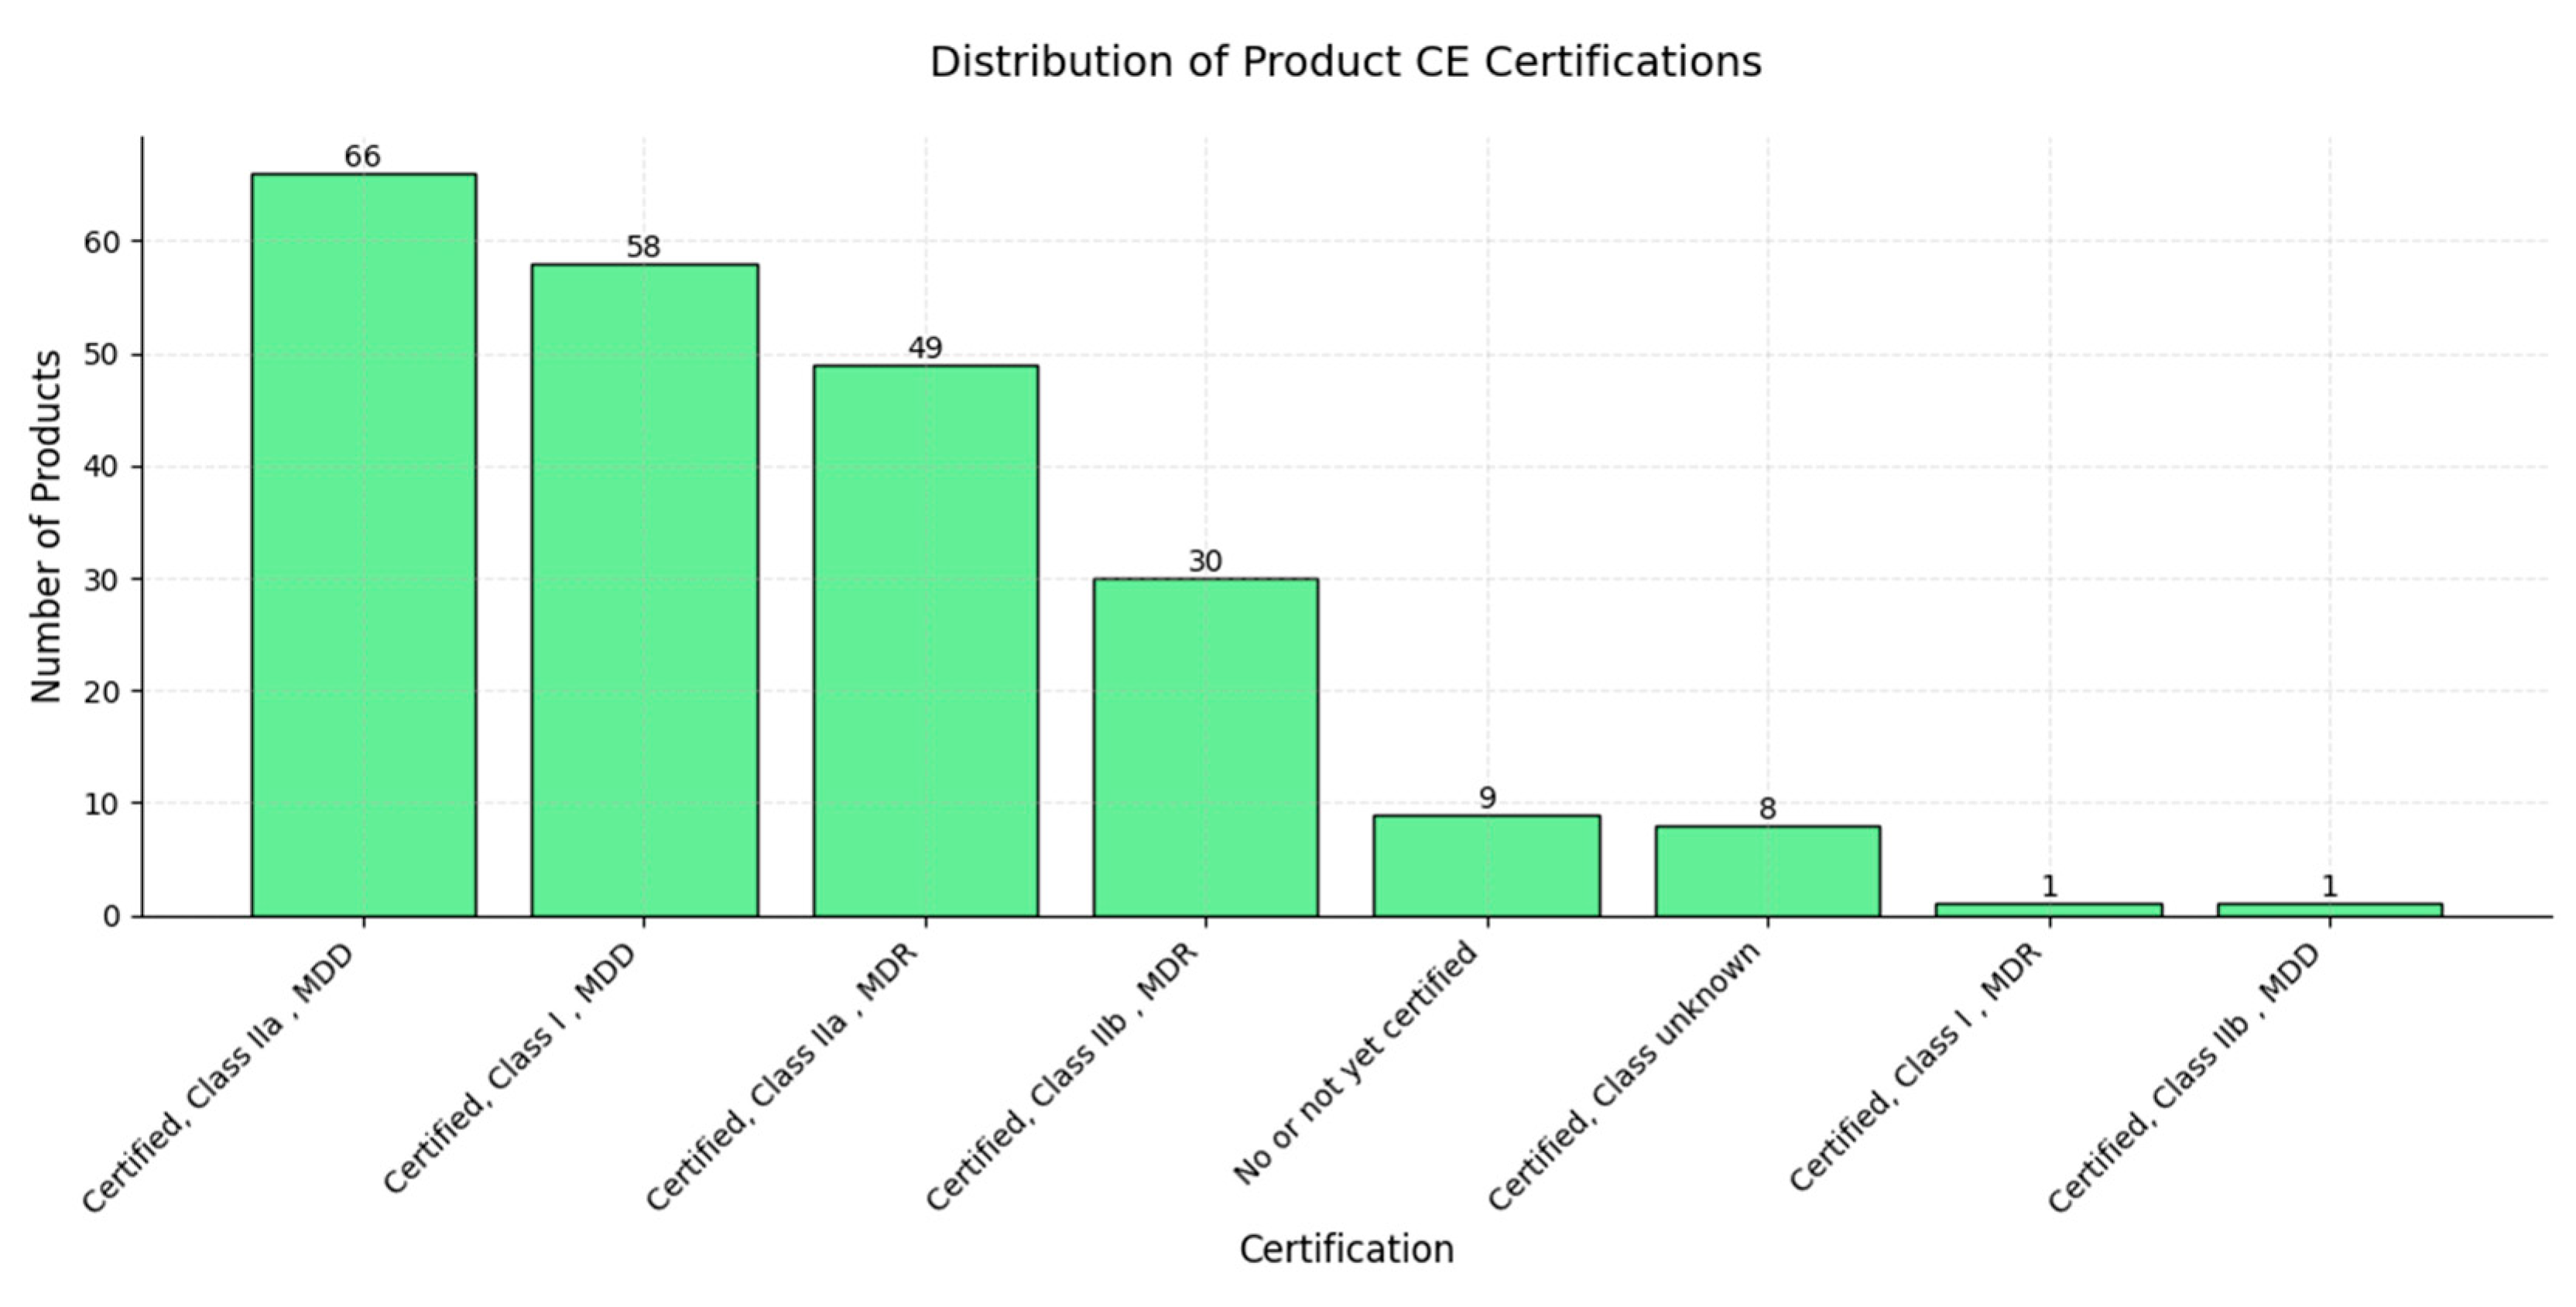

9. Review of AI Products Used in Radiology: Status in 2024